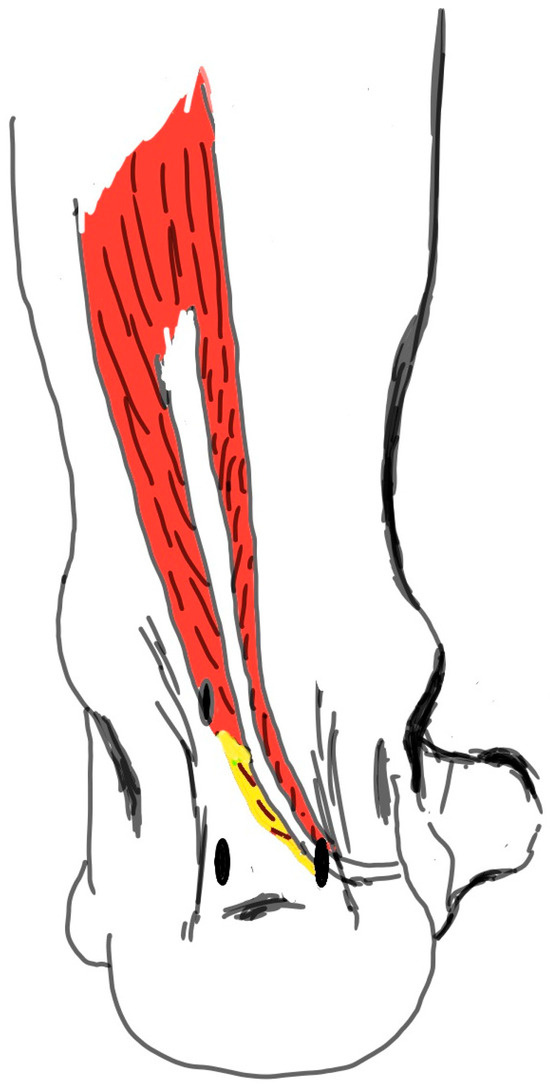

Structured Multi-Modal Rehabilitation Program for FHL Tendinitis and Os Trigonum Excision: A Case Report

Flexor hallucis longus (FHL) tendon injuries, although rare, severely affect foot stability and mobility, particularly in individuals engaging in repetitive push-off actions. This case study examines a 27-year-old male who underwent surgical repair for FHL tendon rupture, followed by a structured, multi-modal rehabilitation

Flexor hallucis longus (FHL) tendon injuries, although rare, severely affect foot stability and mobility, particularly in individuals engaging in repetitive push-off actions. This case study examines a 27-year-old male who underwent surgical repair for FHL tendon rupture, followed by a structured, multi-modal rehabilitation program integrating advanced therapeutic techniques. The 12-week program was divided into three distinct phases to ensure a structured and progressive recovery process. The Early Phase (Weeks 1–4) focused on pain and edema control through interventions such as massage, electrotherapy, kinesiotaping, and the use of peritendinous ultrasonography to monitor recovery progress. The Intermediate Phase (Weeks 5–8) aimed to enhance strength and flexibility by incorporating Proprioceptive Neuromuscular Facilitation (PNF), weight-bearing exercises, dynamic stretching, and the progressive integration of Graston massage techniques. Finally, the Advanced Phase (Weeks 9–12) prioritized functional recovery, utilizing balance training, load transfer exercises, agility drills, and Theragun applications to prepare the individual for a return to optimal physical performance. Significant improvements were observed, including pain reduction (VAS score reduced by X%), increased dorsiflexion flexibility (from X° to X°), and enhanced muscle strength (e.g., tibialis anterior strength increased by X%). Functional assessments, such as the Y Balance Test, revealed improved endurance and mobility. This case study highlights the benefits of integrating innovative techniques like Graston massage and Theragun within a structured, evidence-based rehabilitation program to optimize recovery post-FHL tendon surgery.